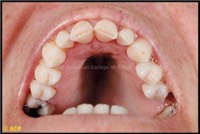

•High palate